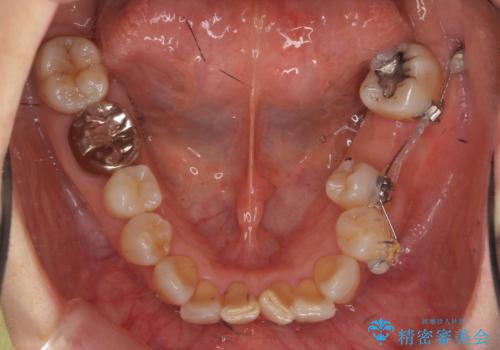

- 左下奥歯の歯ぐきの違和感で来院。

昔神経の治療をした歯が割れてしまっていました。

やむなく抜歯になりましたが、その部分にインプラントを始め希望されましたが、炎症により、骨がなく、かつ歯並びの関係で入れても歯ブラシができずにインプラントも長くもたなそうという診断になりました。

インプラントではなくブリッジにするためには、奥歯の並びを矯正しておいた方がいい状態でした。

抜歯後に部分的にワイヤー矯正を半年ほど行ってから、ブリッジを入れる治療を行いました。